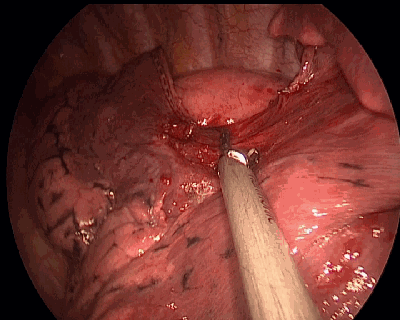

下图为超声刀正在进行肺段血管的游离,精细的操作让血管完全裸化。